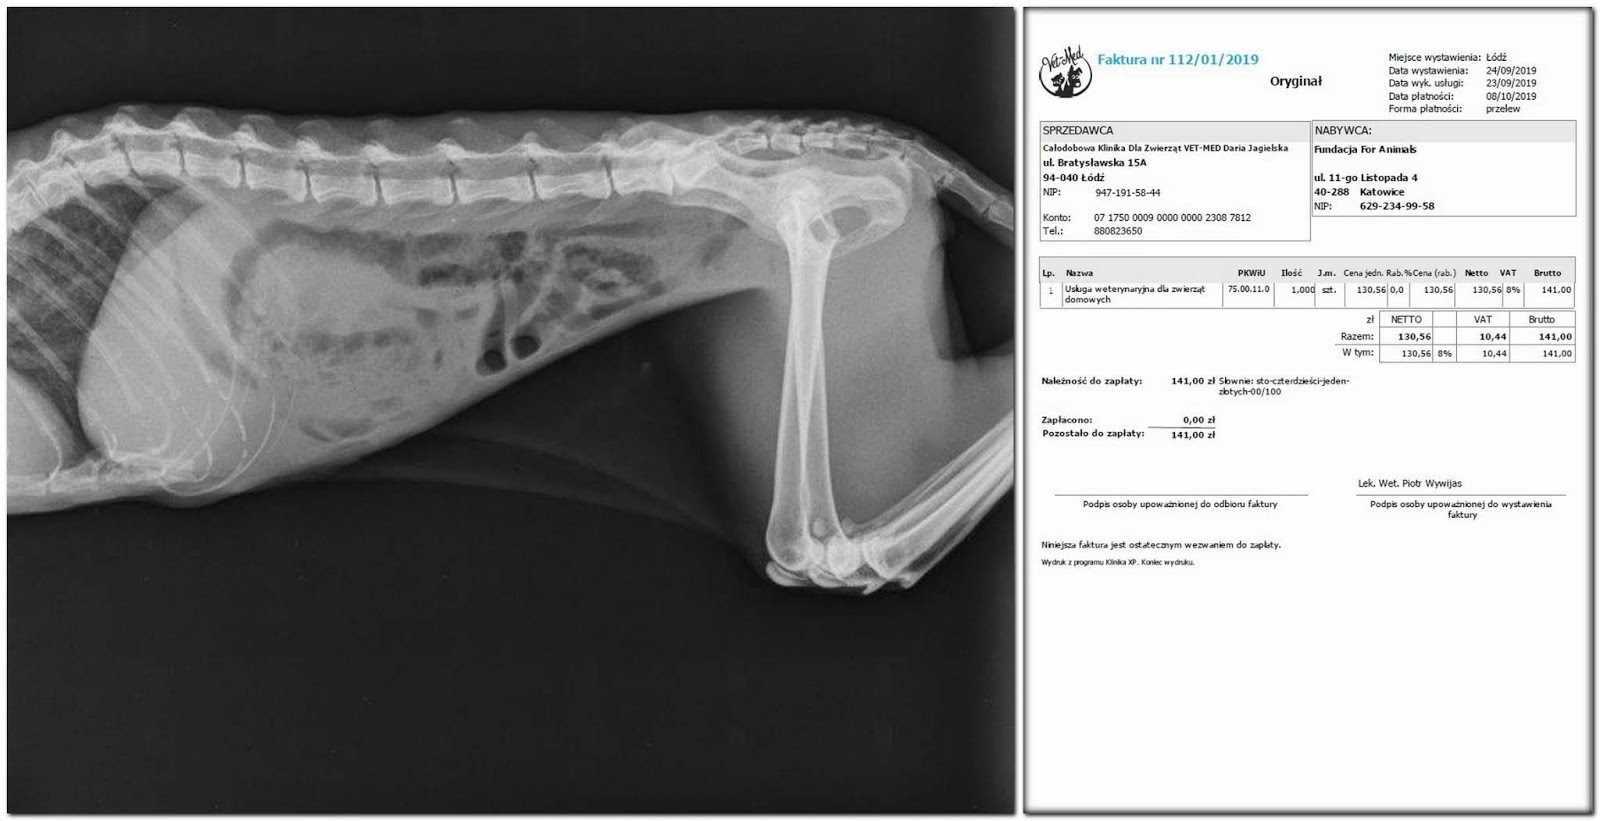

Pojechałam do lecznicy - rtg przełyku z kontrastem - silne

poszerzenie górnego odcinka. Czyli to, co się w pyszczek wkładało,

zostawało tam, nie szło dalej… Miałam do wyboru kilkunastoletnią

kotkę zagłodzić albo uśpić..

Został

rachunek….

Obyło

się bez cięcia - kolejne zdjęcia rtg robione co kilkanaście

godzin pokazały przemieszczanie się gazów. I słówko o fakturze,

prawie symbolicznej - Szefowa przejęła się kocim nieszczęściem,

potraktowała nas bardzo ulgowo - dziękujemy.